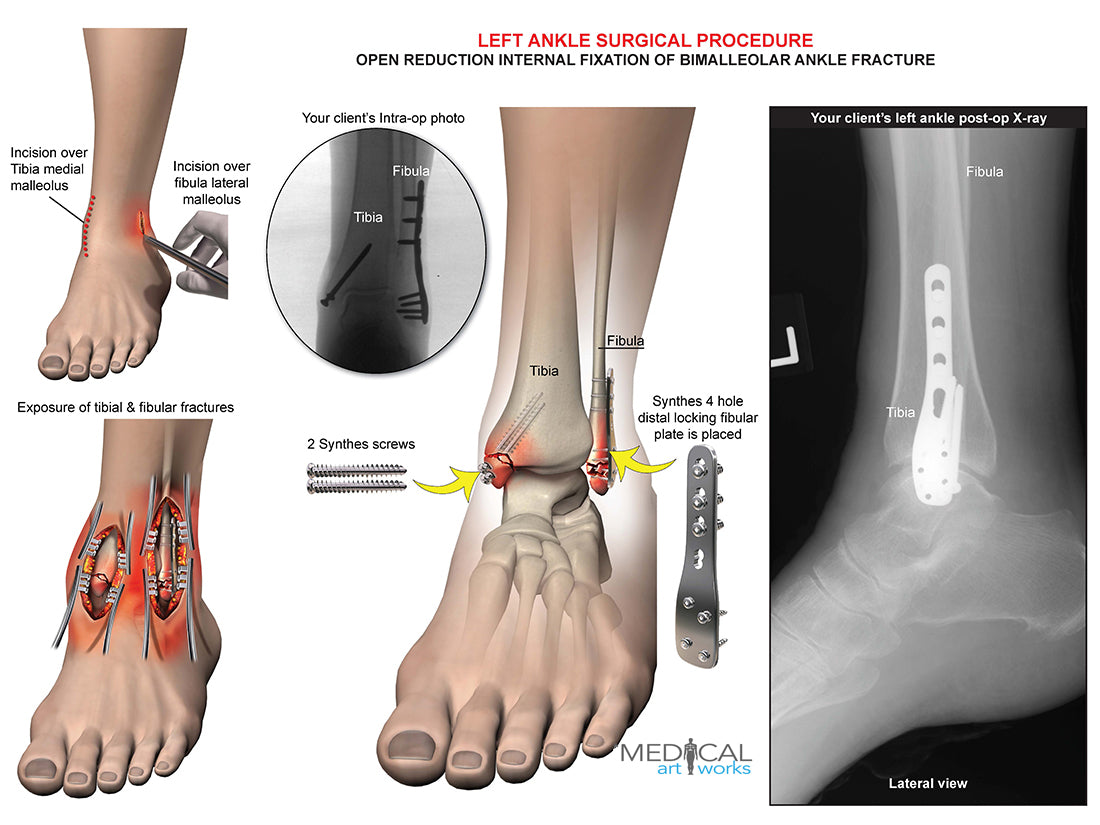

Left ankle and tibia bimalleolar fracture -ORIF

Left ankle and tibia bimalleolar fracture -ORIF

Open reduction internal fixation of bimalleolar ankle fracture. Synthes 4 hole distal locking fibular plate is placed, 2 Synthes screws. Add you own client's post-op x-ray.